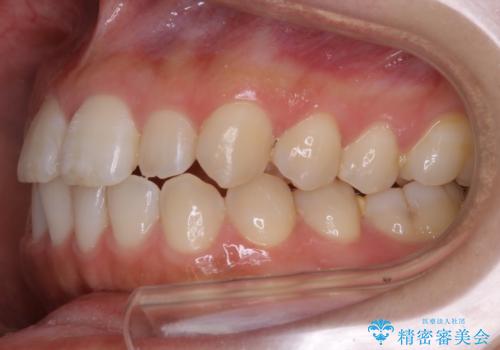

【非抜歯】部分矯正でも治る 前歯の反対咬合

- 前歯にガタつきを主訴にご来院されました。

奥歯の嚙み合わせに問題がほとんどみられなかったため、インビザライン ライトパッケージでの部分矯正を行うこととなりました。

今回のケースでは奥歯の噛み合わせに問題がほぼみられなかったため、前歯の位置のみに焦点を当て部分矯正を行いました。